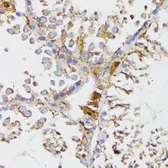

Images

Description

Applications

Reactivity